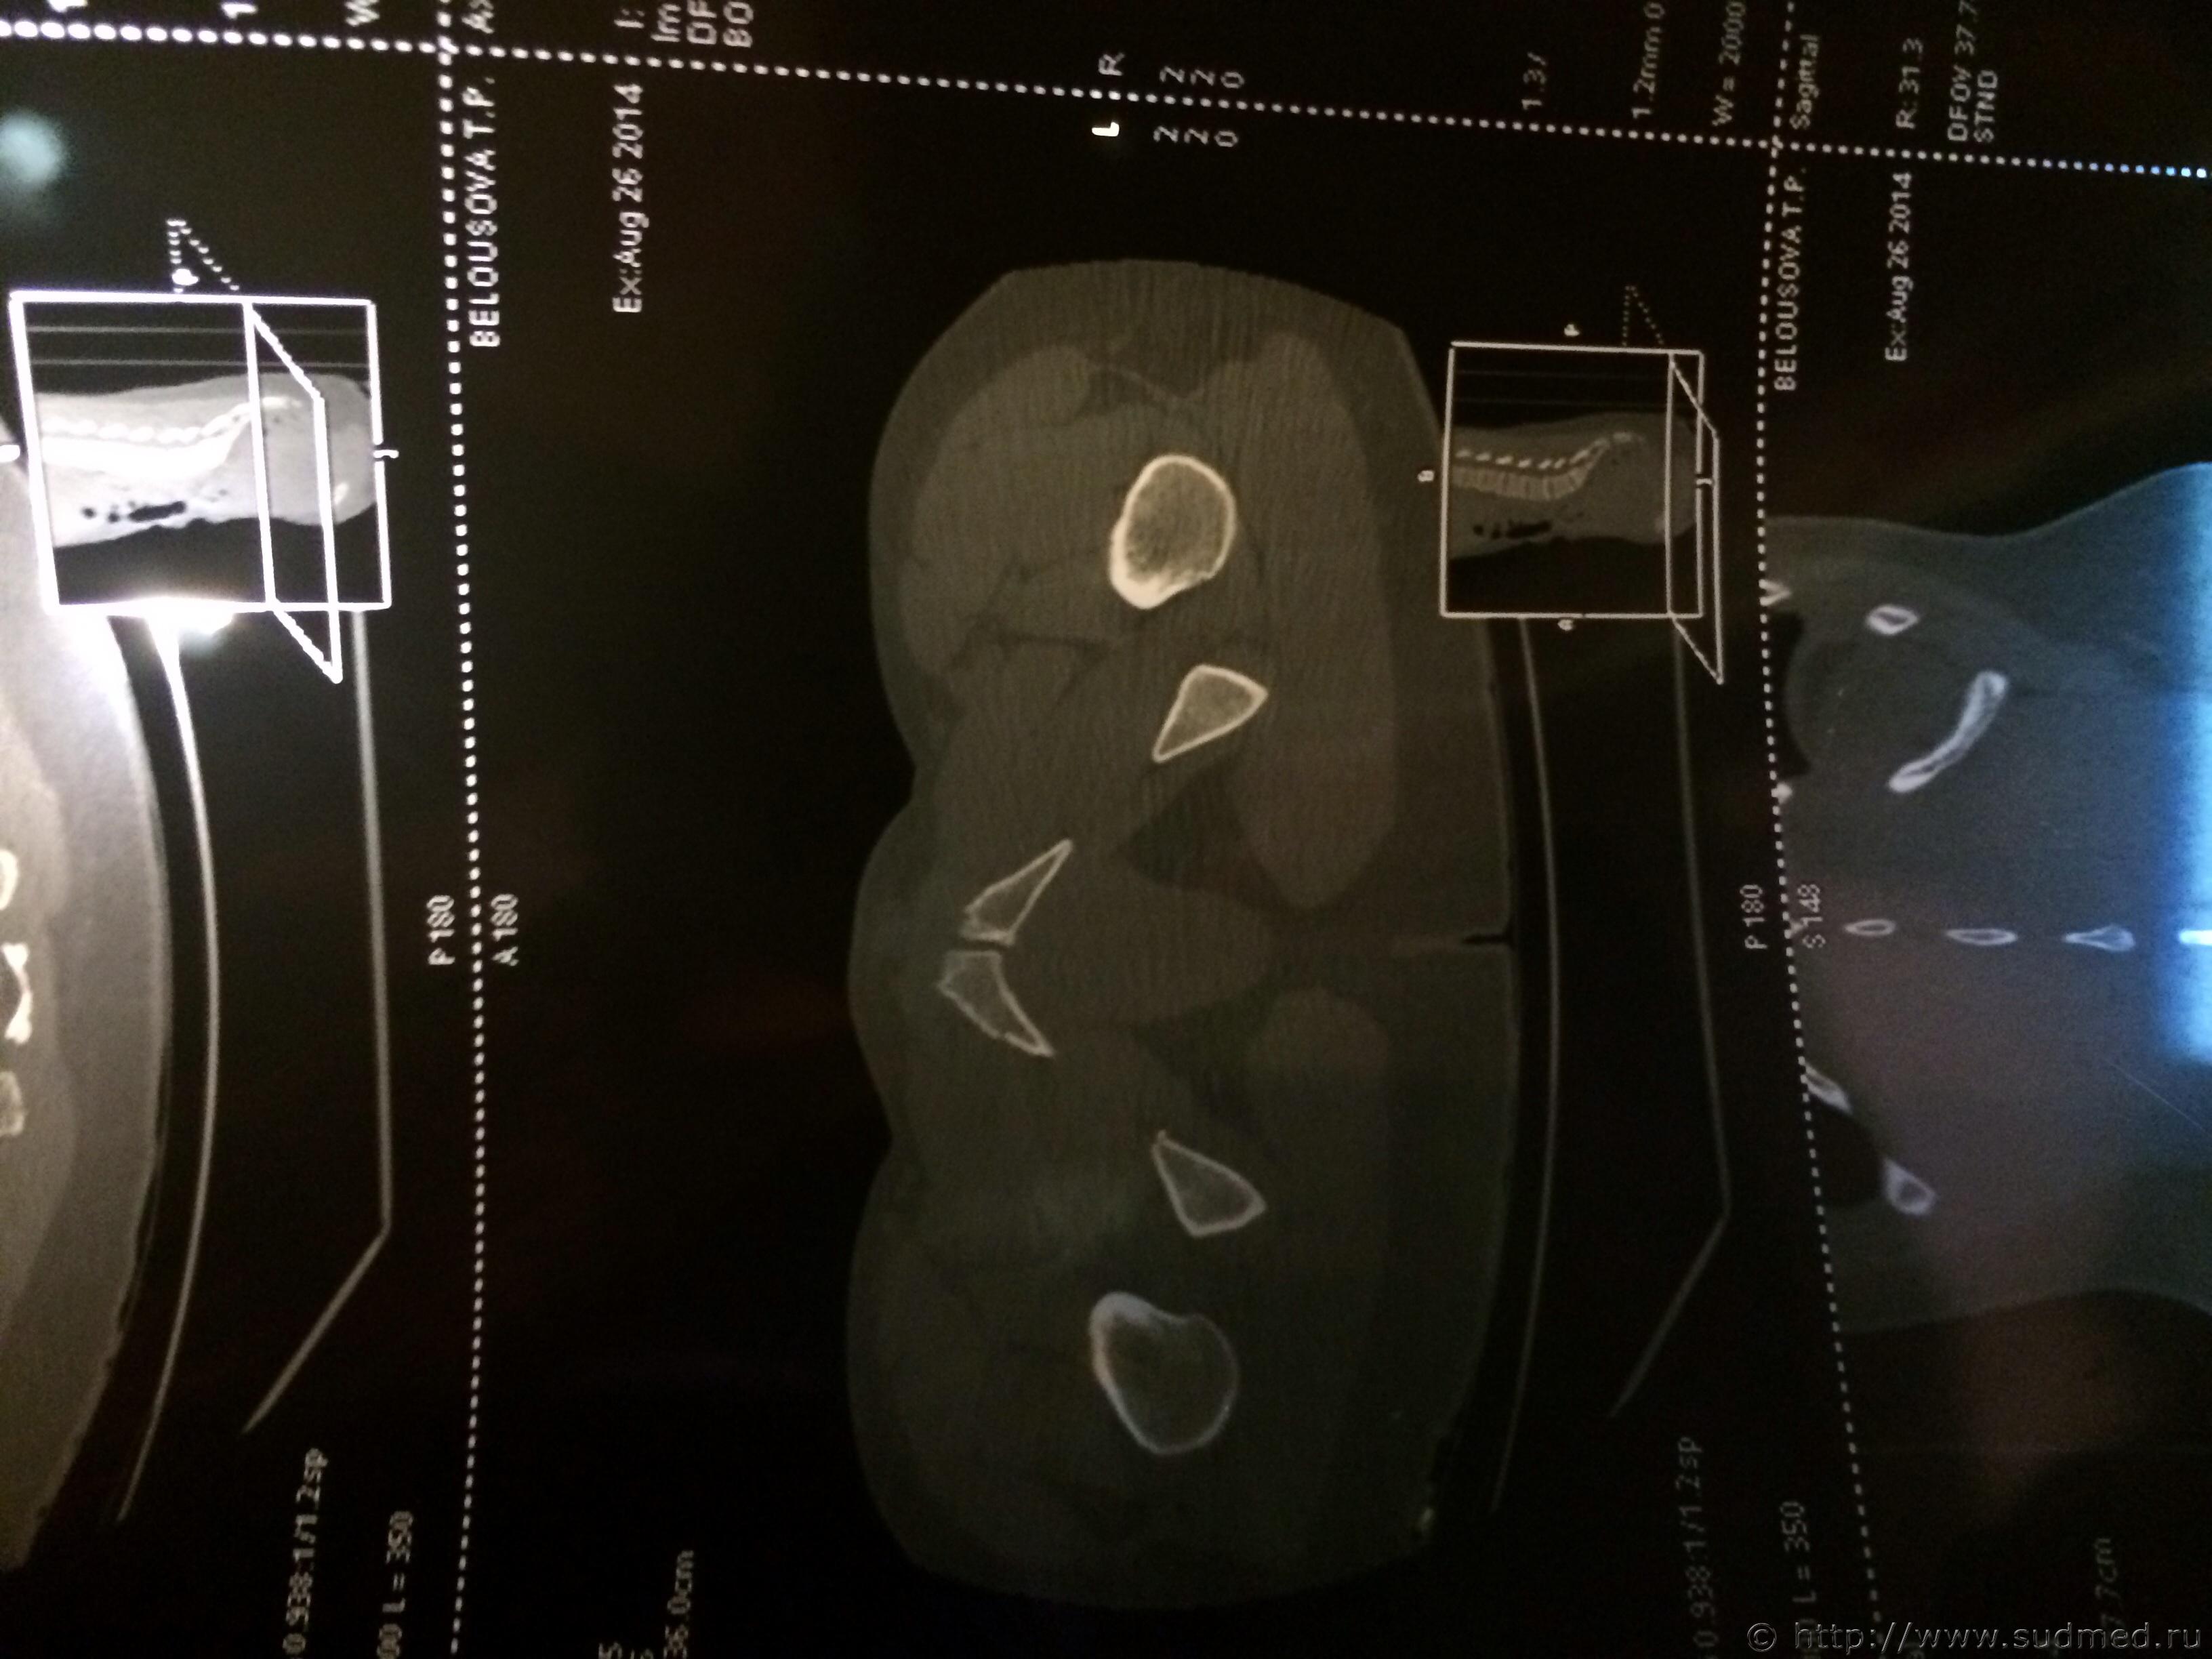

Спасибо! У меня результаты КТ, ошиблась)

КТ

Как мне видится - вертикальный перелом крестца. Тяжкий вред.

Впрочем, оставляю небольшую вероятность, что я не видел все сканы, да и качество их здесь, разумеется, хуже, чем изображение на пленке или на экране компьютера у врача, работающего на томографе.